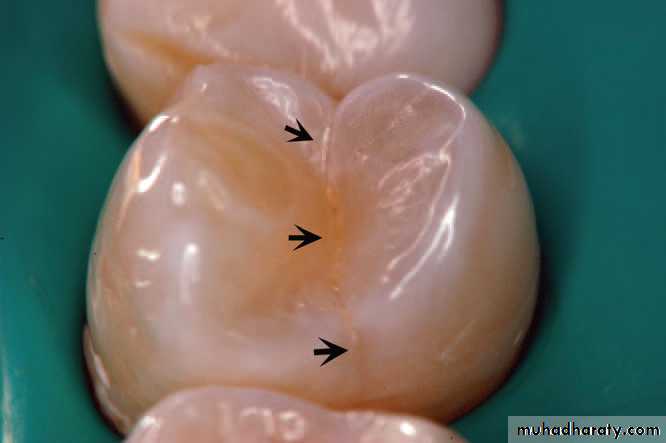

Bite test using a wooden wedge revealed pain in tooth 24.A crack was observed under transillumination . On the occlusal surface of tooth 24, from a mesial to distal orientation.

Using a rubber dam, the crack was better visualized bygiving a contrasting color to background and keeping the tooth

dehydrated.

a): Transillumination was useful to confirm the defect removal during the cavity preparation, until no more cracks were visualized.

b): Completed MOD cavity preparation